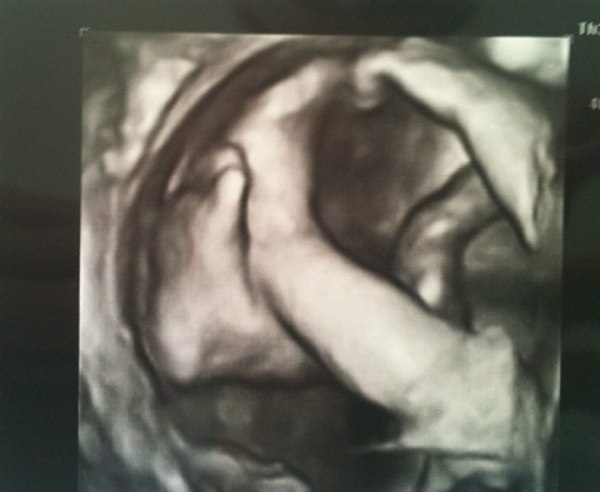

Billede 3 ligger hun med benene på NØJAGTIG samme måde som Milas ALTID ligger;-)

Billede 4 kan man tydeligt se det er en pige :-)